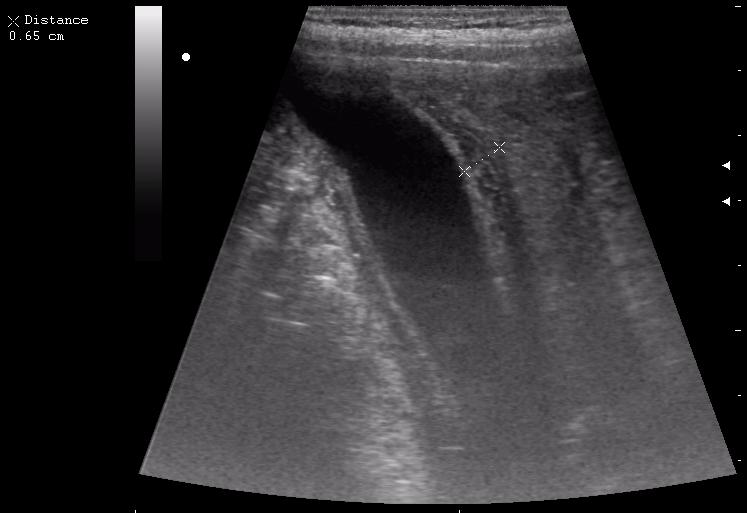

наезд большой черной Прады на маленькую (13кг) 5-летнюю девочку.

получает Медаксон, рабочая версия - изменение желчного пузыря вследствии травмы (шепотом - рекомендация хирургу сменить антибиотик)